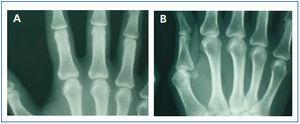

En enero de 2006, presentó HPTS grave (con niveles más elevados de iPTH que los presentados en los meses anteriores). La ecografía paratiroidea reveló una imagen seudonodular hiperecogénica en la zona posteromedial del lóbulo tiroideo izquierdo, que era compatible con una hipertrofia de la glándula paratiroidea. Una serie radiológica mostró signos de hiperparatiroidismo en los huesos de ambas manos y muñecas y CV en las arterias radiales e interdigitales. En la mamografía se observaron múltiples CV lineales en ambas mamas (figura 1A, figura 2A, figura 3A y figura 4A; imágenes de las manos y de las glándulas mamarias en 2006).

Durante este período, se pudo observar que en la serie radiológica las calcificaciones de la arteria interdigital habían desaparecido y que el hueso presentaba un aspecto más estructurado (figura 1B y figura 2B; imagen de la mano, 2007). También la mamografía mostró una regresión de las CV. Las calcificaciones lineales iniciales fueron sustituidas por calcificaciones irregulares (figura 3B y figura 4B; glándulas mamarias en 2007).

La regresión es evidente en las imágenes mamográficas, en las que se observa cómo la calcificación lineal fue sustituida por zonas más pequeñas de calcificación parcheada e irregular. En las imágenes se pone de manifiesto la claridad con la que puede observarse la presencia de CV en las mamografías, lo que permite realizar un seguimiento preciso de la evolución de las mismas. Es, por tanto, una técnica útil, económica y accesible para el diagnóstico y el seguimiento de las CV en mujeres con ERC8,27. La presencia de CV en la mamografía se considera un marcador de riesgo cardiovascular en la población general, relacionado con aterosclerosis y diabetes mellitus. Sin embargo, en la población urémica, un estudio recientemente publicado establece la existencia de correlación histológica entre la presencia de CV en la mamografía y la calcificación de la capa media de las arterias28. Mientras que la calcificación intimal se relaciona fundamentalmente con ateromatosis e inflamación, la calcificación arterial medial guarda una mayor relación con la ERC y las alteraciones metabólicas asociadas5. En el caso que presentamos, al tratarse de una mujer joven sin factores de riesgo cardiovascular añadidos, se podría pensar que la calcificación presente en las arterias mamarias estuviera más en relación con la propia ERC y ser de predominio medial. De ser así, se podría justificar la regresión observada de la calcificaciones mamarias al controlar de forma adecuada las alteraciones del EMO-ERC, regresión tan difícil de observar en otros pacientes, en quienes CV intimal y medial confluyen como consecuencia de la interacción de otros muchos factores, lo que hace más difícil conseguir el deseado efecto de la regresión.

Figura 3. (A) Imagen radiográfica anteroposterior de la glándula mamaria en el año 2006. (B) Imagen radiográfica anteroposterior de la glándula mamaria en el año 2007.

Figura 4. (A) Imagen radiográfica craneocaudal de la mama en el año 2006. (B) Imagen radiográfica craneocaudal de la mama en el año 2007.